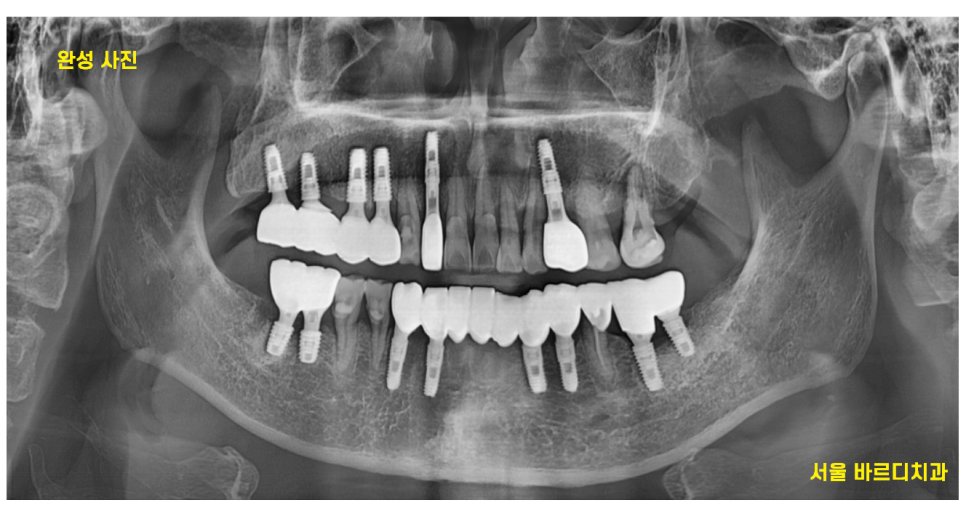

윗니 4개 임플란트

아랫니 6개 치아

총 10개의 강일동 임플란트 치료를 하셔야했습니다.

당일에 10개의 임플란트 식립으로

치료 계획을 수립

미리 CT를 통하여

식립 예정 부위를 분석하였기 때문에

하루에 다수 치아 수술이 가능했습니다.

강일동 임플란트 10개 식립

문제 없이 끝내드렸습니다 .